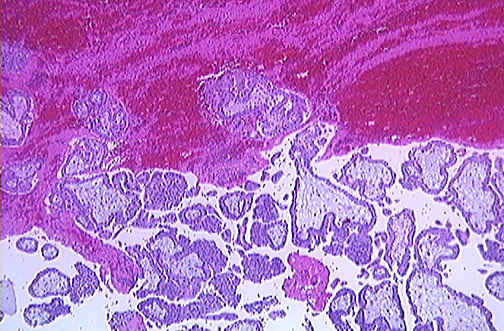

Most common presenting symptom? Most common site of metastasis?

Uterine bleeding

Lungs

(Think: trophoblasts built to invade vessels –> get stuck in lung capillaries)